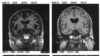

Внутренняя часть импланта преддверно-улиткового нерва

Создание полностью искусственного глаза – дело будущего, а заменить электроникой слуховой нерв можно уже сегодня. Такая система разработана в США: микрофон улавливает звук, затем сигнал поступает в носимый за ухом микрокомпьютер, где трансформируется в цифровой сигнал и достигает собственно импланта, который в свою очередь напрямую стимулирует преддверно-улитковый нерв, отвечающий за передачу слуховых импульсов.